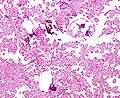

Micrograph of a choroid plexus papilloma. H&E stain.

Plexuspapillom Detail